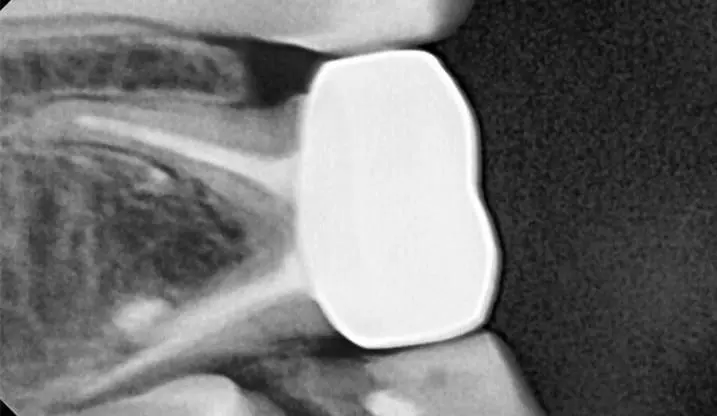

Тимчасові зуби мають ряд особливостей, які не характерні для постійних. Саме тому дитяча ендодонтія відрізняється від дорослої і просте перенесення технік роботи з постійних зубів на тимчасові призводить до серйозних помилок і ускладнень. Наш курс створений для того, аби лікарі впевнено орієнтувались у діагностиці, лікувальній тактиці та її реалізації. Для цього ми розглядаємо питання особливостей анатомії тимчасових зубів, перебігу патології ендодонту тимчасових зубів. В курсі детально подані протоколи лікування, інструменти та матеріали, які використовують для терапії пульпи та кореневих каналів тимчасових зубів. Також дані чіткі критерії визначення терапевтичної чи хірургічної тактики лікування тимчасових зубів. А відеодемонстрація на фантомі та клінічному прийомі дозволить втілити опрацьований матеріал в практику максимально ефективно.